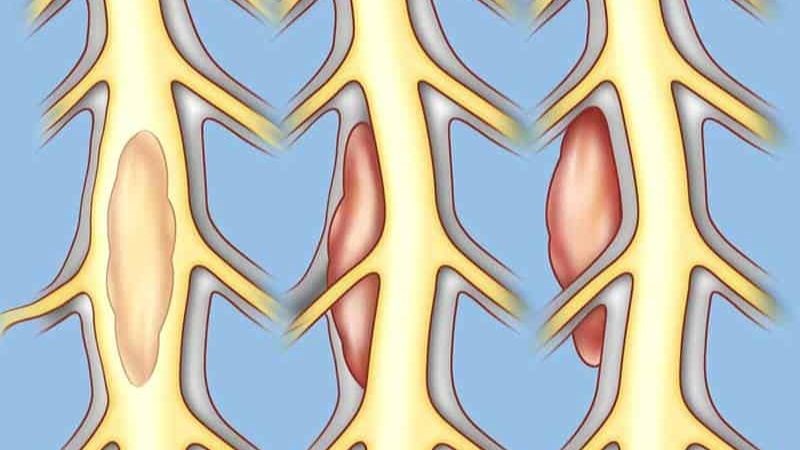

Sarcoma sụn là bệnh ung thư trong đó các tế bào ung thư có nguồn gốc từ tế bào biến đổi tạo ra sụn. Sarcoma sụn là một loại thuộc nhóm các bệnh u xương và mô mềm được gọi là sarcoma.

Các tế bào ung thư Sarcoma sụn có nguồn gốc từ tế bào biến đổi tạo ra sụn